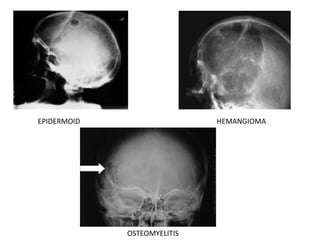

Epidermoid tumors

• Congenital inclusion of epithelial cells within the calvarium

• Well-defined lytic lesions with sclerotic borders

• Not necessarily mid-line

• Intracranial epidermoids may produce a radiolucent shadow mimicking a lytic

lesion.

EPIDERMOID HEMANGIOMA

OSTEOMYELITIS

• Linear nondepressedfractures – Radiolucent lines. Not to be confused with vascular grooves ( ill-defined, undulant course) and sutures ( saw-toothed, expected anatomical location) • Depressed fractures – Area of increased radiodensity surrounded by a radiolucent zone. In children, arachnoid membrane may herniate through the torn dura and pulsations lead to enlargement of the arachnoid collection resulting in Growing fracture. Bulging membranes lead to the formation of a Leptomeningeal cyst. Infections • Rare • Follow trauma or a spread from other sites • Radiographically – mottled irregular lucencies which have well-defined borders and associated swelling of the scalp. Epidermoid tumors • Congenital inclusion of epithelial cells within the calvarium • Well-defined lytic lesions with sclerotic borders • Not necessarily mid-line • Intracranial epidermoids may produce a radiolucent shadow mimicking a lytic lesion.